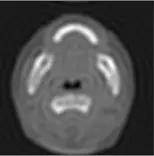

- 頻譜影像(右上):為原始影像經傅立葉轉換後的結果(頻譜空間)。在頻譜圖中,中心亮點代表低頻訊號(Low frequencies),主導影像的整體對比度與平滑區域;越往外圍代表高頻訊號(High frequencies),主導影像的邊緣(Edges)、細節與雜訊。

- 選項 C:此為對比度反轉(Inverted / Negative)的影像,骨頭變黑、空氣變白。此為空間域的灰階對映(Windowing/Leveling 或 Look-up table)轉換,並非頻譜高通濾波的結果。

- 選項 D:影像呈現明顯的模糊化(Blurring),邊緣與細節消失。這是保留低頻、濾除高頻的「低通濾波(Low-pass filtering)」結果。若題目的濾波頻譜圖是「中心亮、外圍全黑」,反傅立葉轉換後才會得到此影像。